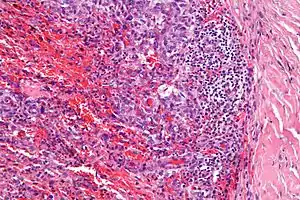

| Micrograph showing an angiomatoid fibrous histiocytoma. H&E stain. |

It is characterized by cystic blood-filled spaces and composed of histiocyte-like cells. A lymphocytic cuff is common. It often simulates a vascular lesion, and was initially described as doing this.[2]